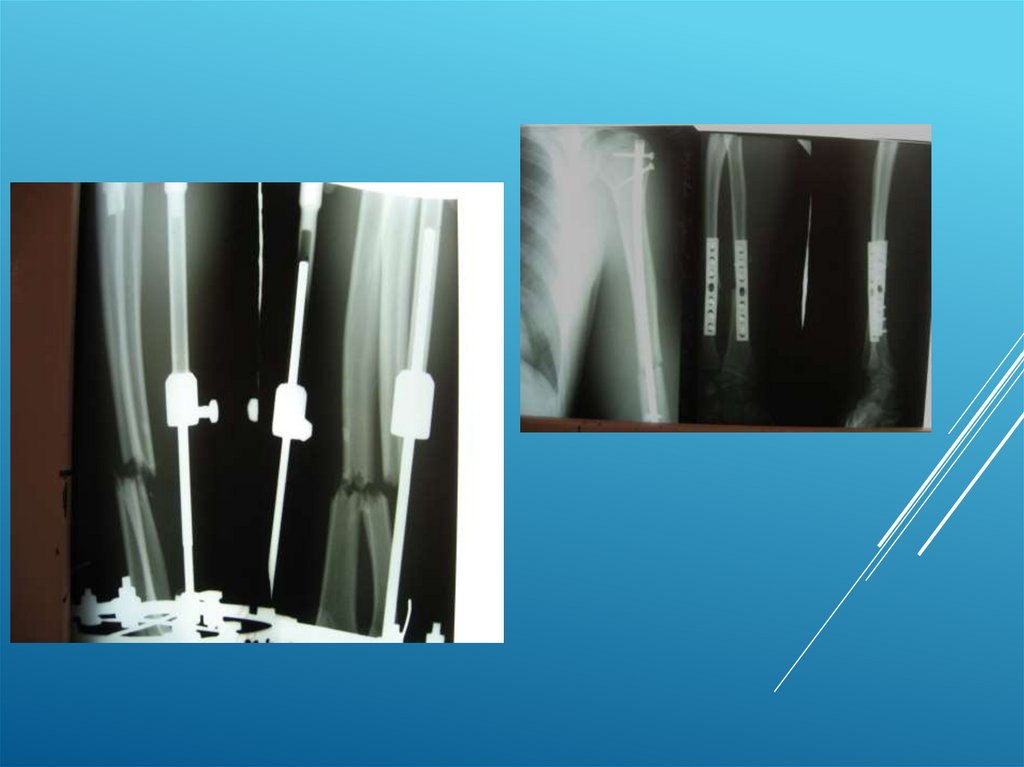

Клинические примеры:

Пациент Д. 32 года

8.

9.

10.

11.

12.

13.